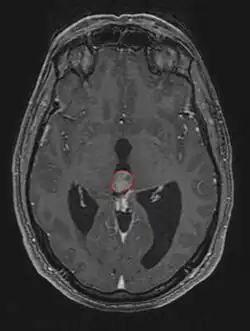

Radiation Oncology/CNS/Pineal

Pineal Gland Tumors

Clinical Presentation

• Determined by the spatial anatomy and direction of growth

• Obstruction of aquaduct: hydrocephalus presenting as headaches, nausea, vomiting

• Compromise of superior colliculus: vertical gaze palsy, pupillary and oculomotor nerve paresis (Parinaud syndrome)

• Work-up includes MRI, CSF, serum markers for bHCG and AFP